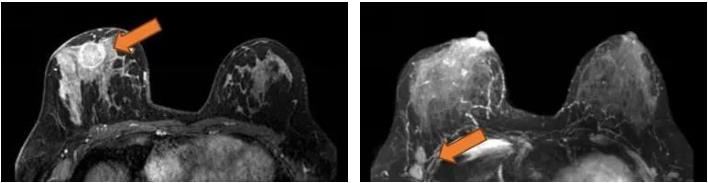

2021.6.28 右乳肿物穿刺活检病理:浸润性乳腺癌,非特殊型,WHO 2级NST  ER(-),PR(-),HER2(3+),Ki67(70%)。

图4. 免疫组化

2021.9.23右乳癌改良根治术标本:乳腺组织见治疗后反应,可见高级别导管内癌残留,瘤床大小约2.0×1.5×1.5cm,未见脉管癌栓,未见浸润性癌,四周及基底切缘未见癌,乳头未见癌,疗效评估(MP 5级)腋窝淋巴结0/11。

ER(-),PR(-),HER2(导管内癌3+),Ki67(20%)。

图8. 术后免疫组化

术后诊断:右乳癌术后(pT0N0M0)